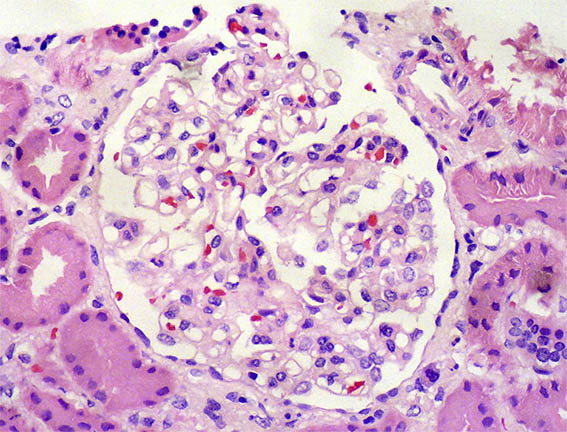

Con diagnóstico de síndrome nefrótico, se hace biopsia renal. Observe las imágenes.

Figura 2. H&E, X200.